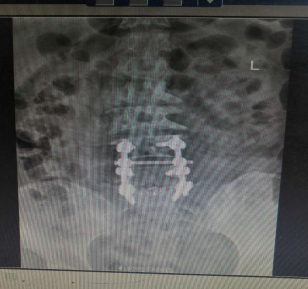

入院讨论后予在全麻下行腰4、5、骶1椎弓根螺钉内固定+腰5滑脱复位+腰5/骶1髓核摘除并Cage植入椎间植骨融合术。

术后影像资料:

1598324087611785.png

专家指导

针对此病例诊断及治疗方案,杨述华教授指导如下:

首先此病例手术做的非常好,展示了武冈展辉医院骨科专家精湛的手术技术。

此病例的诊断也很正确,腰椎滑脱需要采取手术治疗进行复位。

此手术一个切口四个手术,需要减压、复位、固定、植骨,植骨是最重要的。近年来临床上不主张百分百复位,此病例若百分百复位,会有一定的症状。